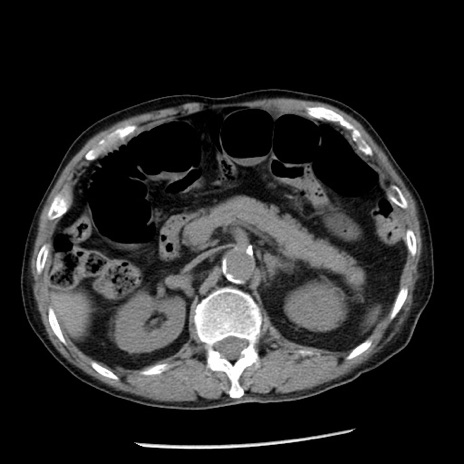

症例26(横断像)

【症例】80歳代男性

【主訴】嘔吐

【現病歴】昨晩2回嘔吐あり、今朝になっても嘔吐あり。来院。

【既往歴】胃潰瘍

【身体所見】意識清明、BT 37.6℃、BP 166/95mmHg、HR 100bpm、SpO2 97%、腹部:平坦・軟、腸蠕動音聴取良好、圧痛なし。

【データ】WBC 21900、CRP 1.46